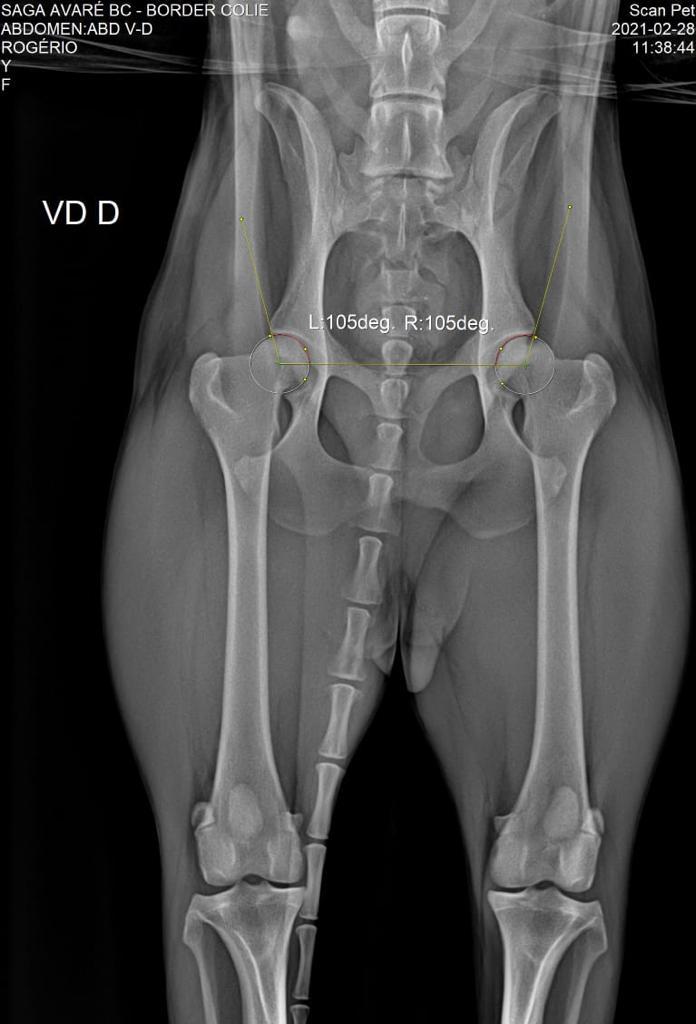

DISPLASIA

28/02/2021

ADEQUADO GRAU A

SCANPET

LAUDO

CHAPA